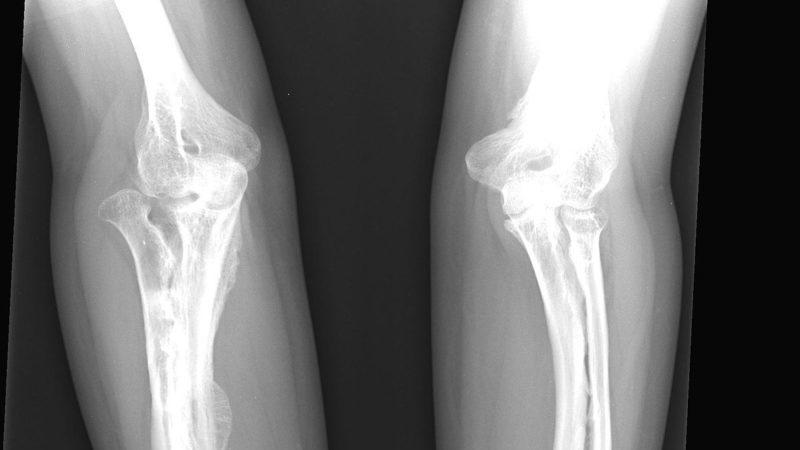

Хрустальная болезнь (фото):

- рентгеновское исследование, чтобы определить наличие переломов;